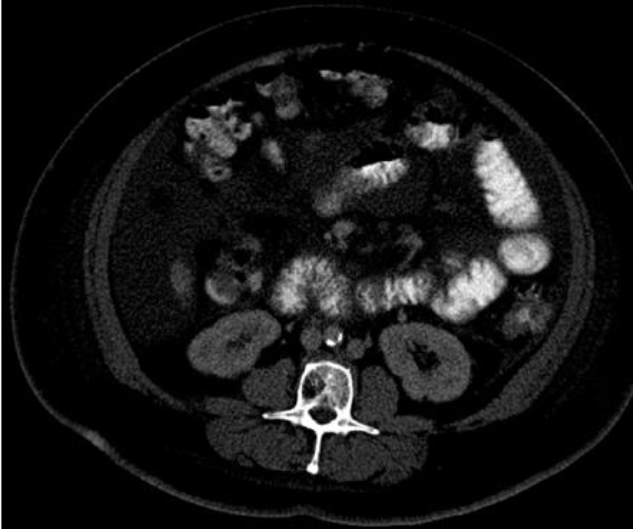

·If you have trouble visualizing whether tissues are muscle or another organ/fascia, you can use the color scheme tool (Tools Color Scheme) to darken the image to better visualize the muscle.

·If the color scheme tool does not allow the unknown structures to be adequately visualized, go back to the entire original series of images to see what those unknown structures might be. The best way to do this is to find the L3 image in the entire series of images and follow the structure downward and upward to help get a clearer picture of what it could be.